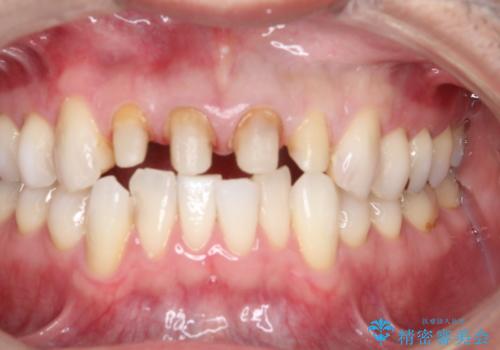

- 前歯のかぶせ物を自然な色味のものにしたいとのことで、来院されました。

保険適用のかぶせ物が装着されており、適合も悪く、変色している状態でした。

土台からの、再治療を行い、オールセラミッククラウンの装着を行う計画としました。